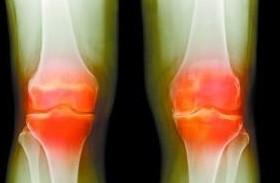

发生风湿性关节炎的话最明显的症状就是疼痛非常厉害。假如出现疼痛的话可以服用一些镇痛的药物。这样或许有所帮助,比如药物有如芬必得、阿司匹林等非常典型的镇痛药物。不过虽然这些药有镇痛消炎的作用,但...[详细]